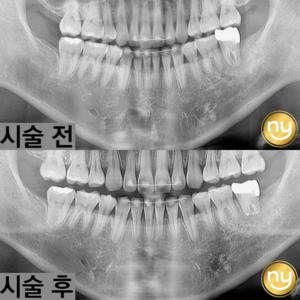

울산안아픈치과 신경치료 후 염증 치아재식술로 해결해요! 안녕하세요. 울산안아픈치과 뉴욕연합치과입니다. 임플란트가 워낙 보편화되고 선호하는 분들이 많아지고 있지만, 자연치아를 살리고자 하는 수요도 급상승하고 있는 추세입니다. 위 환자분은 충치가 많이 진행되어…